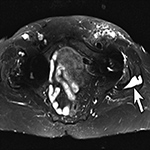

Inversion Recovery Imaging. (A) Axial spectral adiabatic inversion recovery (SPAIR) image used during MR examination of the abdomen and pelvis demonstrates large regions of susceptibility due to bilateral metal-on-metal hip arthroplasties as this technique is highly sensitive to field inhomogeneities.

| Inversion Recovery Imaging. (B) Axial STIR MR image in the same patient reveals fluid-signal pseudotumor (arrow) adjacent to the left greater trochanter, which was obscured on prior examination. |